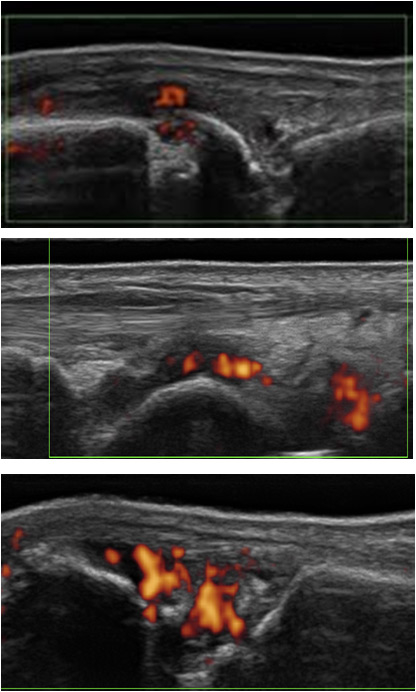

Figure 2

Synovitis grade 1-3 on B mode: proximal inter-phalangeal joint.

The Swiss SONAR score analyses 22 joints in order to include approximately the same joints as the DAS, but excluding the thumbs and shoulders. These joints were excluded because they could be the site of common rheumatological problems not related to RA (osteoarthritis, rotator cuff lesions and other disorders). The score includes the palmar view of joints for B-mode, with a semiquantitative assessment in accordance with the Berlin score (fig. 2) and the dorsal view in PD-mode (fig. 3). The scanning time is between 10 and 15 minutes including PD evaluation. The cartilage thickness and presence of bony erosions and tenosynovitis can be assessed optionally.

Figure 3

Synovitis grade 1-3, PD activity: dorsal view of a metacarpo-phalangeal joint. Presence of an erosion.